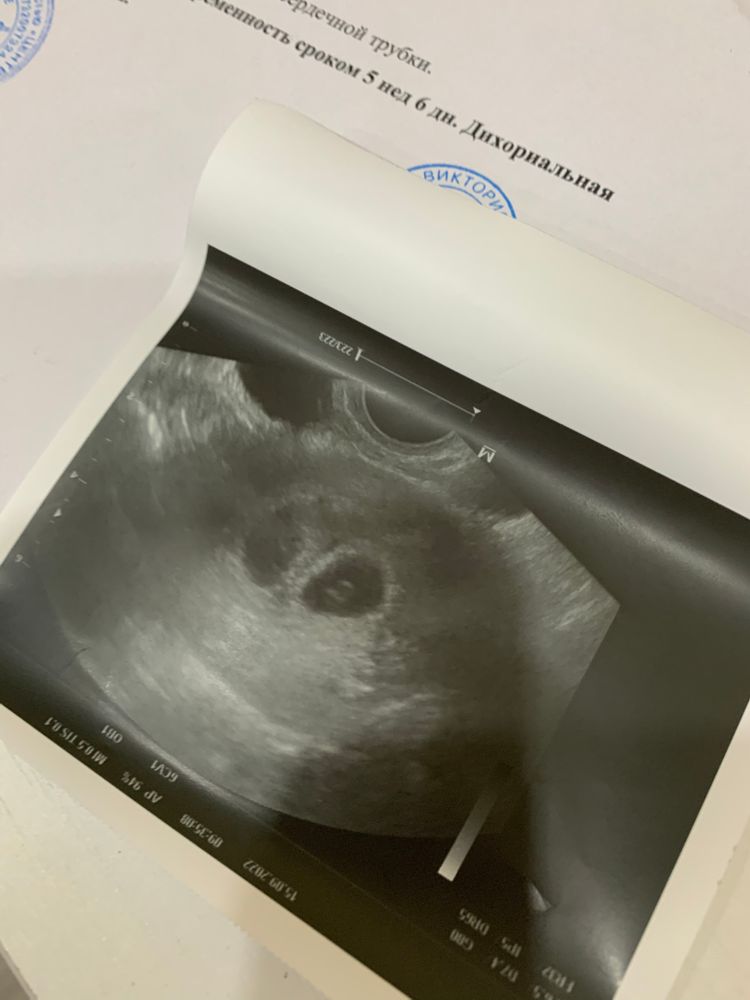

Первое узи🙏21 ДПП